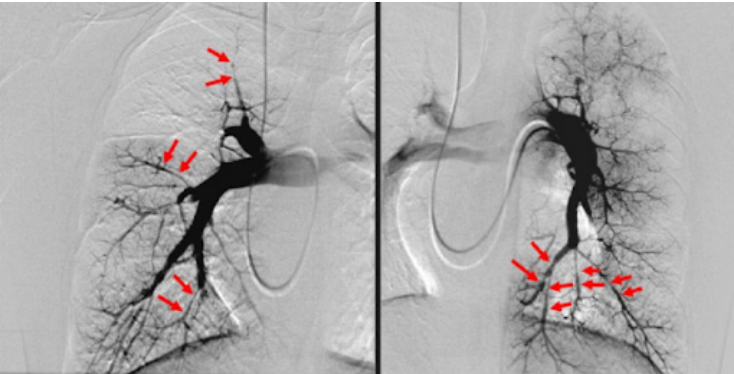

Arteriografia Pulmonar

- Antigamente considerada o padrão-ouro.

- Hoje é raramente usada devido ao risco de mortalidade (0,5%) e complicações (1-5%).

- Diagnóstico: É feito pela presença de trombo após 6 meses de anticoagulação plena (tempo mínimo obrigatório), avaliado por ECO-TT, Angio-TC, Cintilografia V/Q ou Arteriografia.

- Cirúrgico (Preferencial): Tromboendarterectomia.

- Percutâneo: Angioplastia pulmonar.